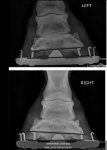

I 5-stage vetted her and she "passed", but with some comments that she has slightly bad conformation on one of her forelegs. As you can see in the x-ray attached, the bones in her lower left leg are a bit bent.

The vet wasn't too concerned about it - but did say it's not ideal and could wear down those joints more than usual. He also suggested the farrier can make it better.

I 5-stage vetted her and she "passed", but with some comments that she has slightly bad conformation on one of her forelegs. As you can see in the x-ray attached, the bones in her lower left leg are a bit bent.

The vet wasn't too concerned about it - but did say it's not ideal and could wear down those joints more than usual. He also suggested the farrier can make it better.